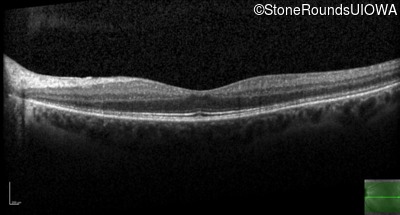

Optical Coherence Tomography - Right - 20/32

Exemplar / OCT Stack

OCT Stack